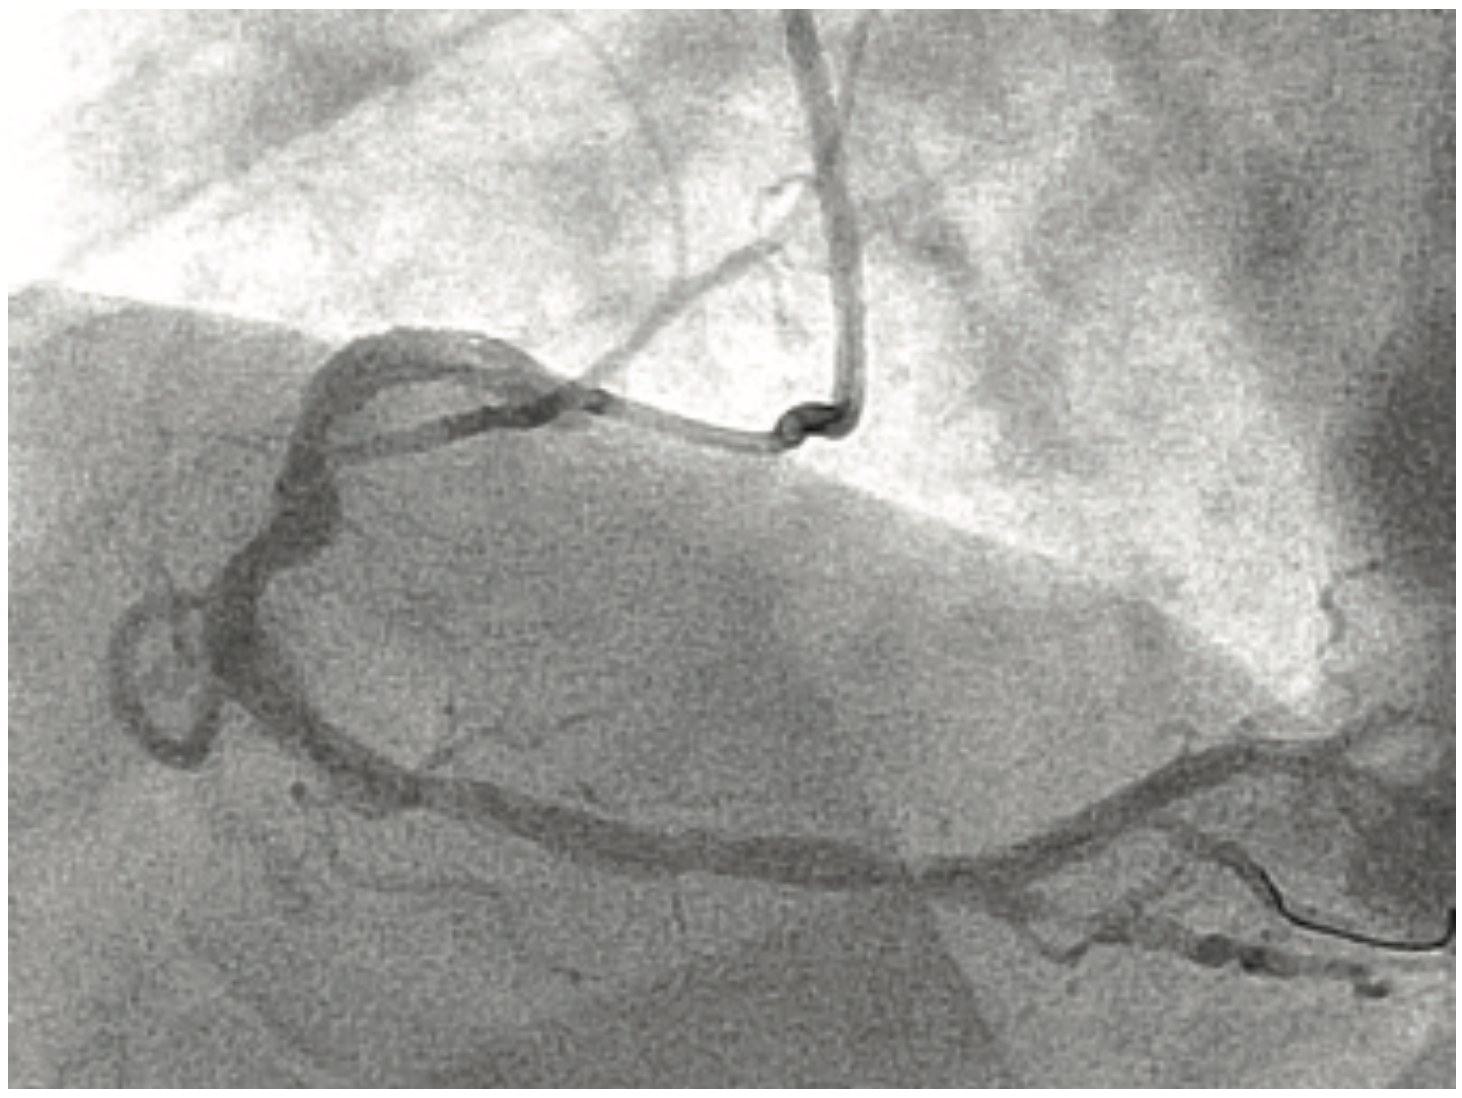

A 51-year-old male without prior cardiac history presented with chest pain that started 24 hours prior that was persistent and varying in intensity. He was still having intermittent chest pain when he was evaluated in the emergency department. An electrocardiogram showed inferior Q waves without ST elevation. Initial troponin was 19 ng/mL. He was taken to the cath lab with a concern for post infarct angina. Angiography revealed a large RCA with multiple large thrombi in the proximal to mid RCA (Figure 5A). Using a 6 Fr Amplatz left (AL) 0.75 catheter, and a 6 Fr GuideLiner, aspiration thrombectomy was attempted with little success. A 2.0 x 30 mm compliant balloon was inflated at the site of the thrombus to try to disintegrate the thrombus. A second attempt with aspiration thrombectomy through the GuideLiner showed marked improvement in thrombus burden, but persistent ulceration of the proximal RCA (Figure 5B). At this point, it was felt that the best possible reduction of thrombus burden had been achieved and a stent was deployed (Resolute Onyx 4.5 x 30 mm, inflated at 26 atm). Remarkably, after stent deployment, there was no evidence of thrombus or distal embolization. A second stent was placed from the mid to distal RCA (Resolute Onyx 4.5 x 26 mm inflated at 26 atm) due to severe luminal irregularities, with the final result in Figure 5C. Multiple thrombi were visualized on the filtered blood that was suctioned with the 50 cc syringe (Figure 7). A GP IIb/IIIa inhibitor was administered post operatively. The patient was started on optimal medical therapy and was discharged 3 days post-op without any complications.